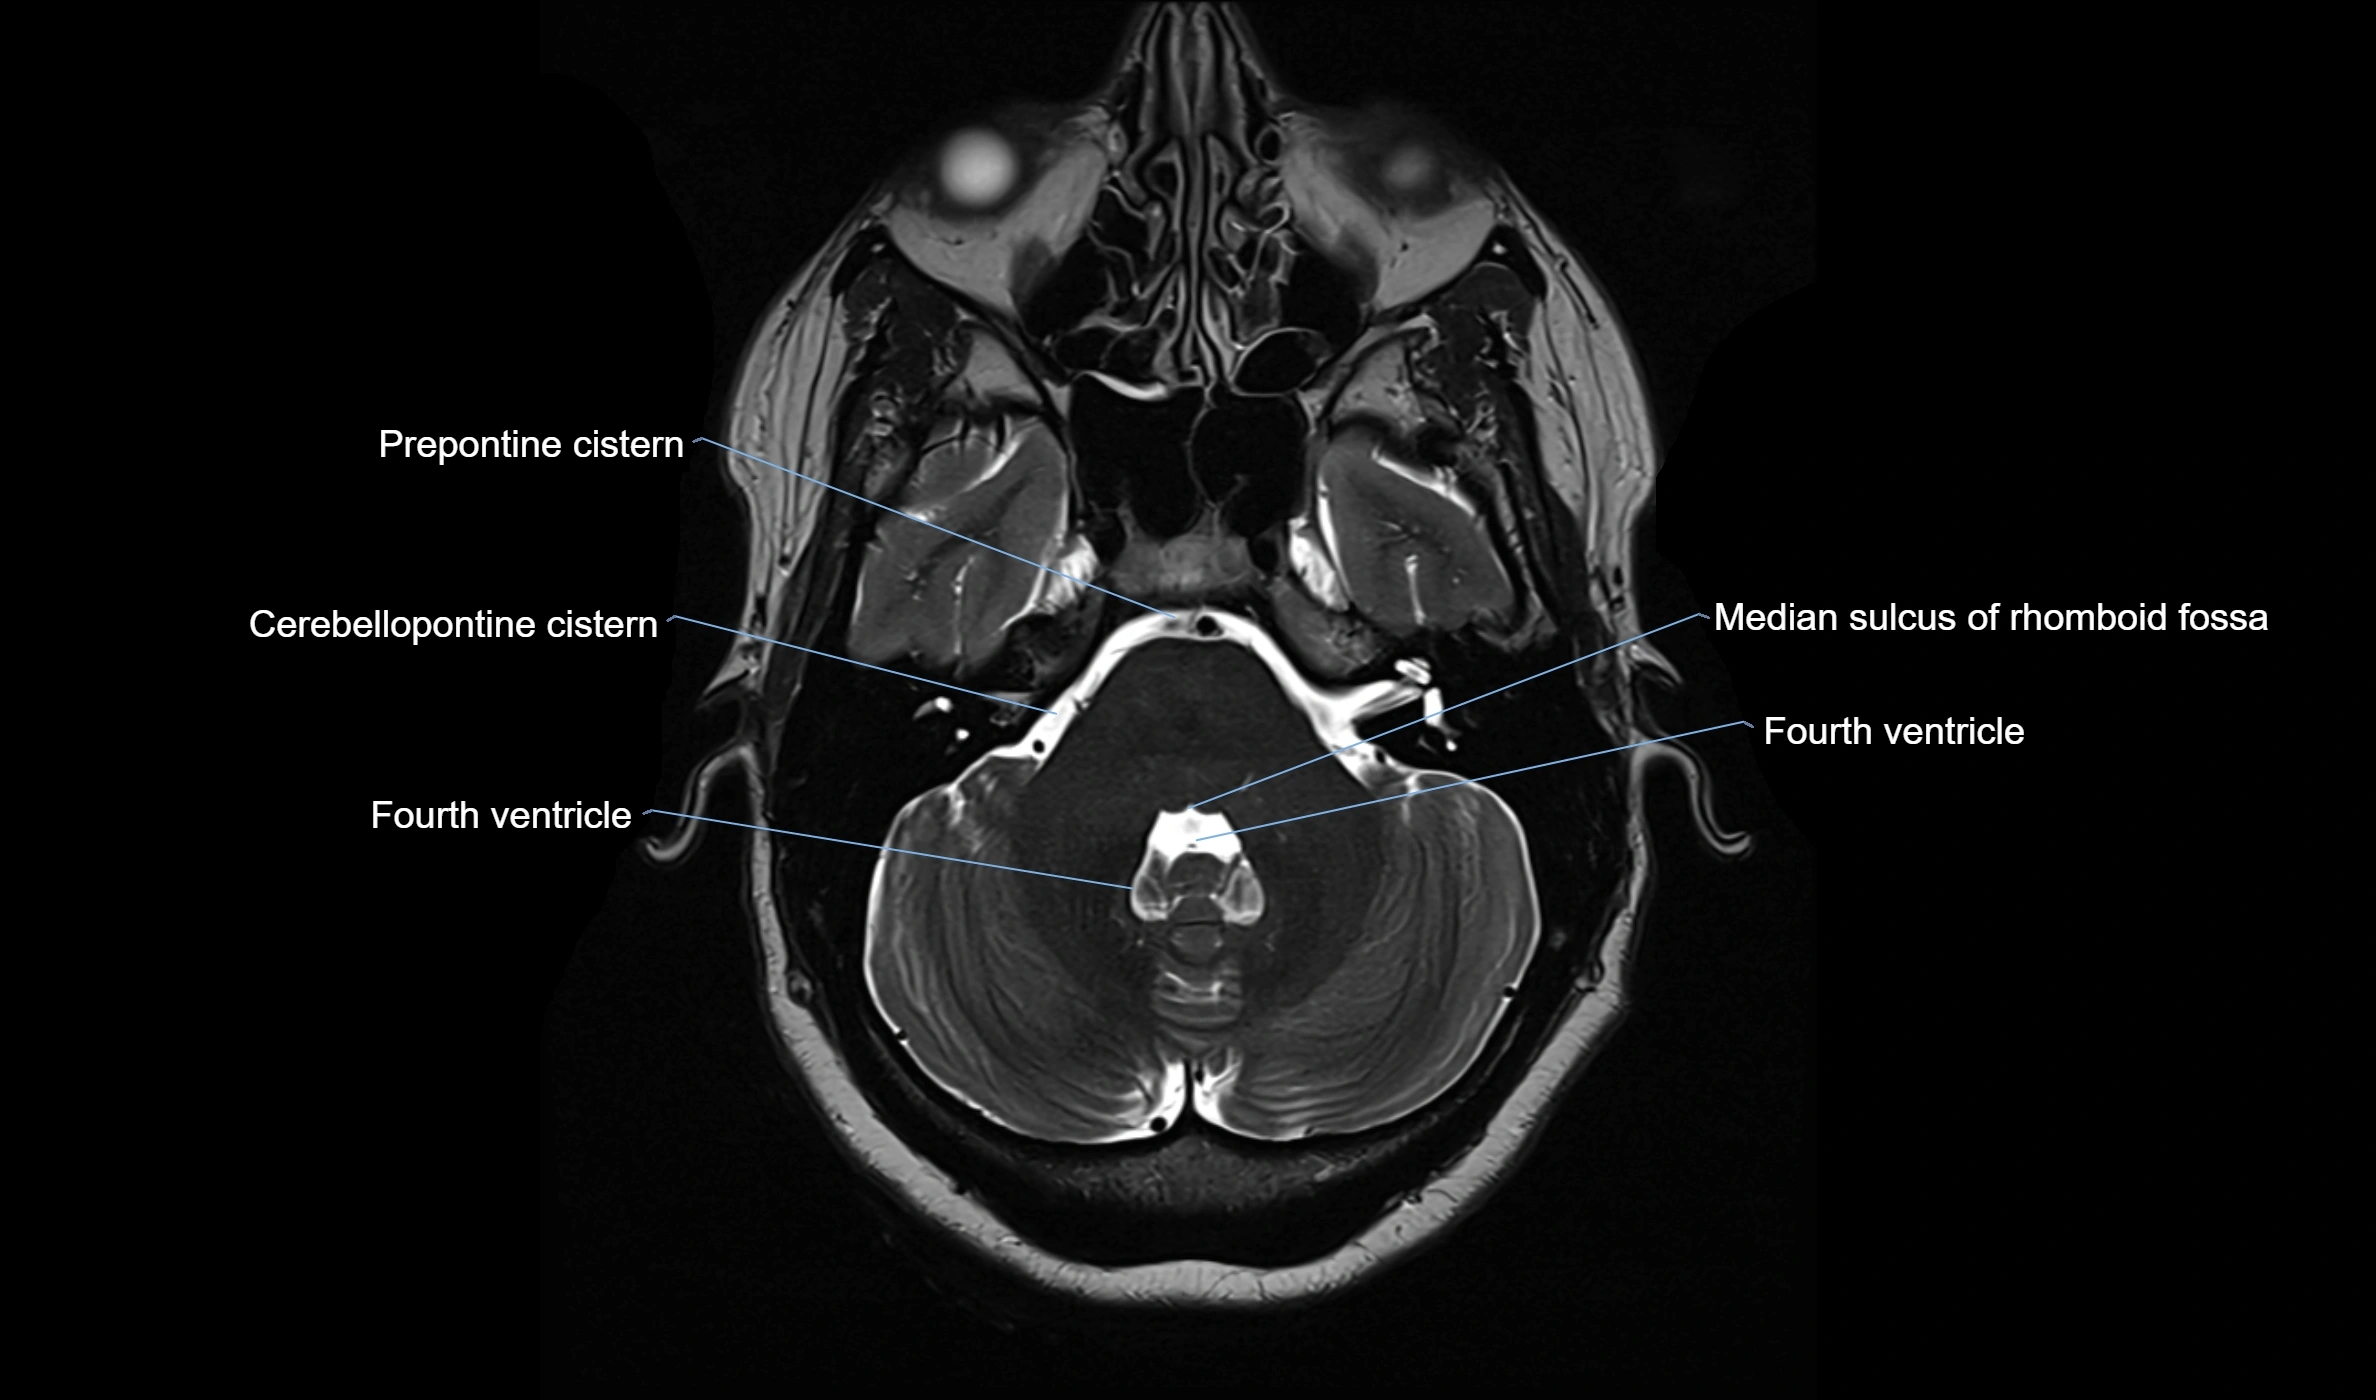

CT image

image